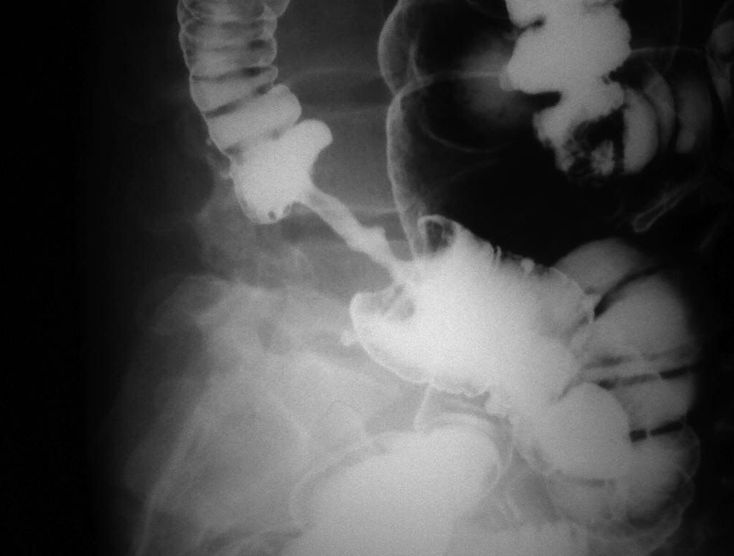

Apple core appearance. s/o ca colon

Colorectal cancer Apple core apearance